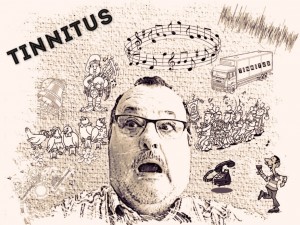

Otologische symptomen. Zijn er otologische (oor gerelateerde) symptomen die al dan niet gepaard gaan met de hoofdsymptomen (tinnitus of oorsuizen, gehoorverlies, een ‘vol gevoel‘ in de oren, een druk in de oren, hyperacusis of het niet goed kunnen verdragen van geluid, …)

Antwoord: Voordat ik problemen kreeg met mijn evenwicht, had ik al last van Tinnitus. Dag en nacht lawaai in beide oren en nog verschillend ook. Bij ENG onderzoeken is gebleken dat mijn linker evenwichtsorgaan steeds slechter wordt ten opzichte van het rechter evenwichtsorgaan.

Tinnitus

Een veel voorkomende ergernis, die ik ondervind, is het constante lawaai in beide oren. Oorsuizen, ook wel Tinnitus genoemd. Je hoort aan een stuk door, dag en nacht, verschillende geluiden. Van een volle volière, een blaaskapel, klokkengeluid, doedelzakspelers, pieptonen etc. En dan ook nog in het ene oor wat anders dan in het andere oor. Er zit totaal geen samenhang in.

Een veel voorkomende ergernis, die ik ondervind, is het constante lawaai in beide oren. Oorsuizen, ook wel Tinnitus genoemd. Je hoort aan een stuk door, dag en nacht, verschillende geluiden. Van een volle volière, een blaaskapel, klokkengeluid, doedelzakspelers, pieptonen etc. En dan ook nog in het ene oor wat anders dan in het andere oor. Er zit totaal geen samenhang in.Ik heb Tinnitus besproken met de KNO-arts, maar deze heeft er verder niets mee gedaan. Het ”hoort” er kennelijk bij. Toen ik nieuwe digitale gehoorapparaten kreeg had ik de hoop dat die ook Tinnitusproof waren. Helaas bleek dat niet zo te zijn. Daarnaast gaf de audicien aan dat het Tinnitusproof nog niet altijd succesvol is. Er wordt dan een tegengeluid door het gehoorapparaat geproduceerd zodat het geluid/ruis wegvalt. Bij een enkeling heeft het wel tot goede resultaten geleid.

De meest voorkomende oorzaken van tinnitus zijn: (bron: tinnitus.nl over Tinnitus)

– Afwijkingen aan het binnenoor;

– Een harde prop oorsmeer in de gehoorgang;

– Problemen met de buis van Eustachius;

– Problemen in het middenoor;

– Overgevoeligheidsreacties van zenuwen op bepaalde geneesmiddelen;

– Afwijkingen aan gehoor- en evenwichtszenuw;

– Afwijkingen aan andere zenuwbanen;

– Een klap tegen het hoofd, hersenschudding en hersenletsel;

– Afwijkingen aan gebit en kaak;

– Afwijkingen aan de eerste en tweede halswervel;

– Afwijkingen in de bloedvaten in het hoofd;

– Hoge bloeddruk;

– Samentrekkingen van spiertjes;

– Erfelijke factoren en ziekten bv. diabetes, multipele sclerose (MS), etc.;

– Ziekte van Ménière;

– Stress, waardoor onder andere hormonale verandering kan ontstaan;

– Plotselinge harde geluiden of langdurig lawaai, ook wanneer dit in het verleden heeft plaatsgevonden.

Voorlopig er mee leren om te gaan…………

Op Tinnitus.nl staat meer informatie over deze aandoening.